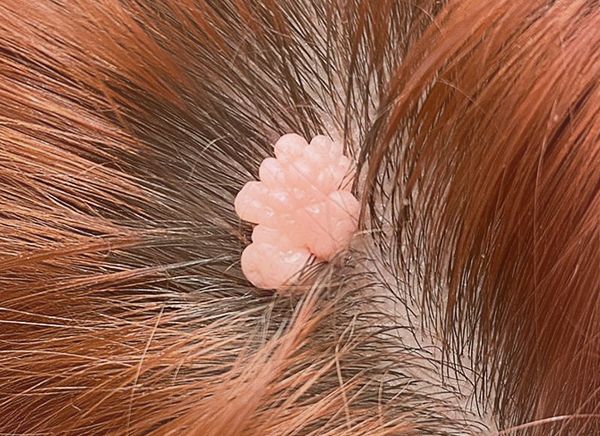

Код мкб 10 атерома головы

Код мкб 10 атерома головы 109 фото